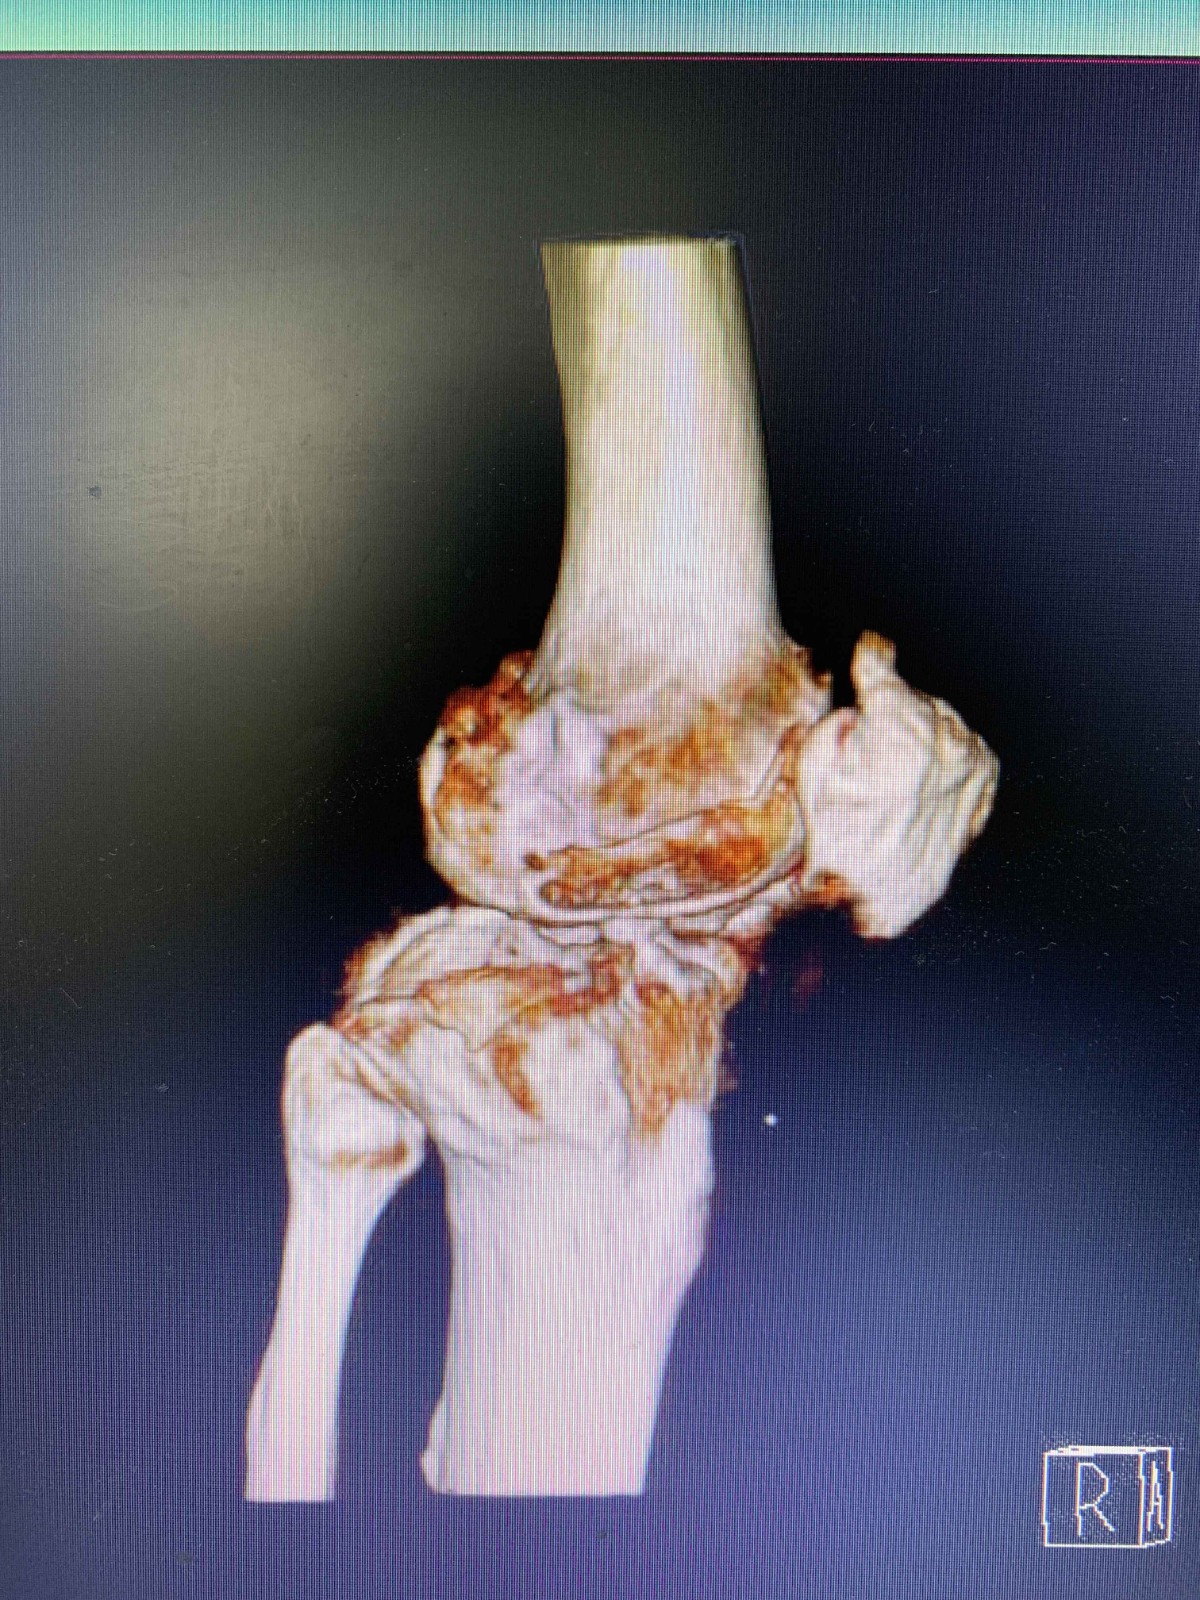

名称: 右膝关节CT平扫+MPR重建

检查日期: 2019-06-29 02:06

图像结果:

结果描述:

右膝关节骨端示骨质增生,骨赘形成;内侧关节间隙明显变窄;关节面欠光整,关节面下示囊变影及片状高密度硬化;髌上囊及关节腔内示片条状液性密度影,其内可见多个小圆形骨样高密度影。胫骨近端内侧示游离骨质密度影,边缘密度更高。

1.右膝关节退行性骨关节病

2.右膝关节积液

3.考虑右膝关节滑膜骨软骨瘤病